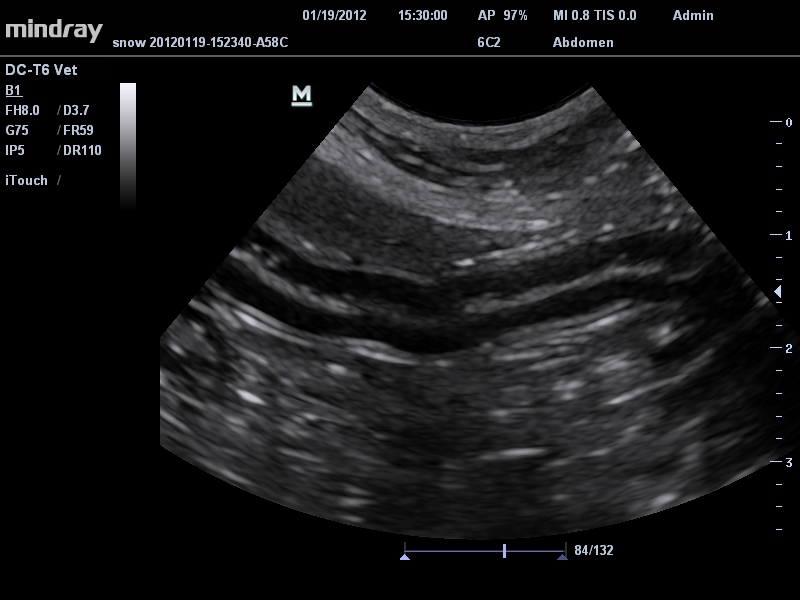

Ветеринария:

Да

• Микроконвексный датчик Mindray 6C2

• Ультраректальный ветеринарный датчик Mindray 6LE5Vs